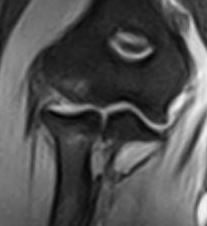

Risonanza Magnetica del gomito- Coronale Gomito

Essendo un esame che sottopone il paziente ad un campo magnetico, se pur basso, controindicazioni primaria e assoluta è la presenza del pacemaker. Inoltre, i pazienti che hanno protesi metalliche in qualsiasi parte del corpo, devono portare documentazione dell’intervento a cui sono stati sottoposti in sede di esame di RM. Il Tecnico di Radiologia insieme al Medico Radiologo, avranno il compito di constatare se la protesi metallica è compatibile con la risonanza magnetica (quindi di materiale non ferromagnetico).

Una protesi localizzata nella sede di esame compromette l’efficacia diagnostica dell’esame poiché NON si riusciranno ad avere immagini di quella zona.